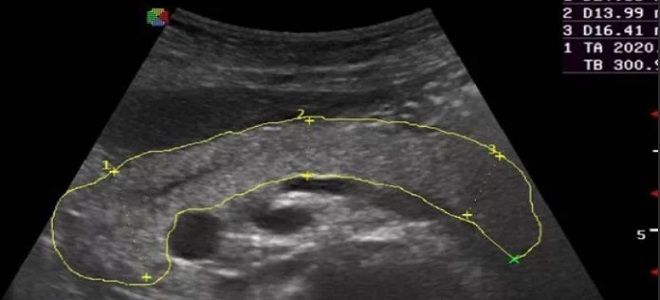

УЗИ поджелудочной железы

УЗИ является наиболее доступным и простым способом диагностики. Изменения в поджелудочной железе на ультразвуковом исследовании четко различаются по размеру и месту расположения. Этот метод предоставляет информацию о положении поджелудочной железы, ее размерах и других характеристиках, необходимых для определения заболевания. Процедура позволяет выявить:

- признаки воспалительных процессов;

- новообразования и различные опухолевые образования;

- наличие кальцификатов.